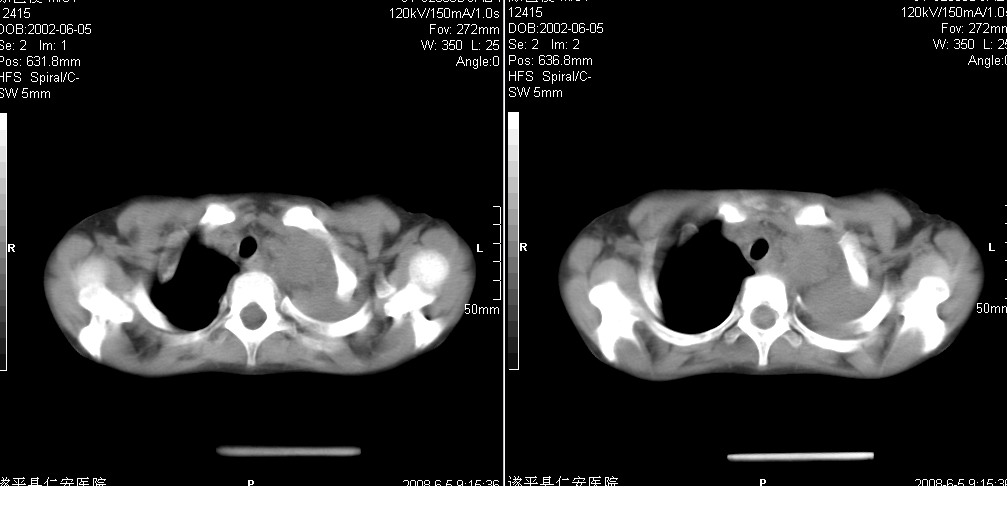

以下是引用xxhwh在2008-6-10 18:40:00的发言:[br]男,6岁,无规则发热一月余,体温在37.8——39度之间。一月前拍胸片示左上肺密度增高影,进行抗炎治疗8天,复查胸片未明显吸收。又改变抗菌素继续治疗半月,照胸片示病灶吸收不明显,行ct检查[br]征象:左上肺前段呈密实影,内可见支气管气像,远侧见絮状模糊影,中上纵隔左移。[br]意见:左上肺前段膨胀不全及感染,考虑为支气管异物或支气管内膜结核所致,[br]建议追问有无异物吸入史,行痰检及ppd检查